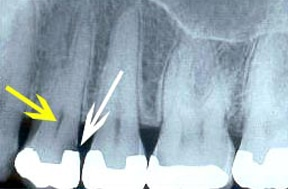

Once you are fully at ease, our dentists carefully remove any existing fillings to access the core of the tooth using high-precision instruments. Throughout the procedure, we rely on advanced imaging tools, including digital X-rays and intraoral cameras, to guide our work and maintain exact accuracy while protecting the healthy structure of your tooth.